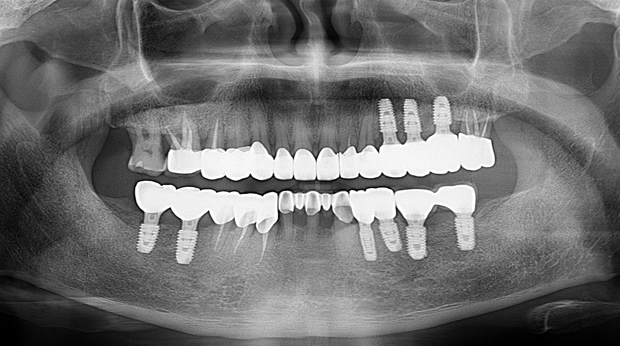

임플란트와 사랑니 발치는 외과적 시술로 잇몸을 절개하는 외과적 시술은

짧으면 짧을 수록 시술 후 붓기와 통증이 최소화됩니다.

치과의사 경력 14년차 구강외과 전문의가 빠르고 안전하게, 아프지 않게 수술해 드립니다.

치과경력 14년차 구강외과 전문의